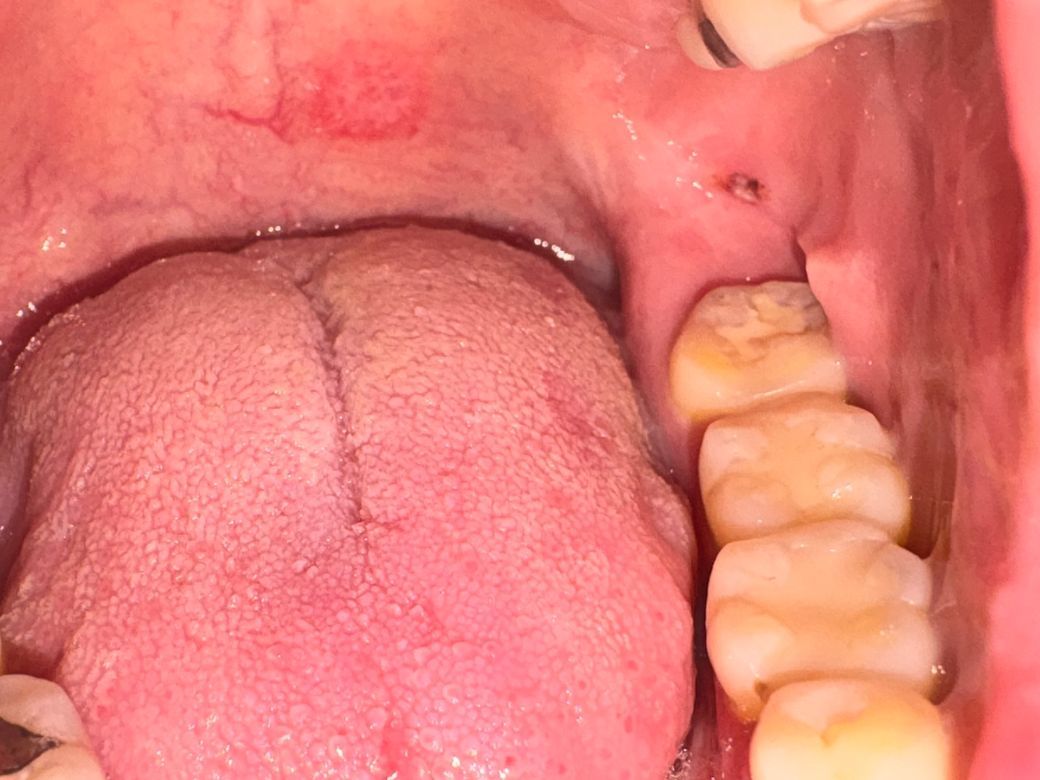

그런데 오늘 입안을 보는데 사랑니쪽에 검은색으로 보이는데 혹시 이게 뭘까요? 갑자기 생겼습니다

만졌을 때 아주 살짝 튀어나와있고 말랑합니다

구내염처럼 하얗지도 않고 통증도 없습니다

피가 고인것처럼 검은색이라 뭘까 싶습니다

• 사진상 병변은 전형적인 구내염(아프타성 궤양) 형태와는 다릅니다. 구내염은 보통 중심이 하얗거나 노란 막으로 덮이고 주변이 붉으며 통증이 동반되는 경우가 많습니다. 현재 병변은 검은색 또는 자주색으로 보이고, 통증이 없으며 약간 돌출되고 말랑한 점을 고려하면 점막하 출혈 또는 혈종(작은 피멍) 가능성이 가장 높습니다.

병태생리적으로는 씹는 과정에서 점막이 미세하게 눌리거나 물리적 자극을 받아 점막 아래 혈관이 터지면서 국소적으로 혈액이 고이는 형태입니다. 특히 사랑니 주변은 음식물 끼임이나 교합 압력이 집중되는 부위라 흔히 발생할 수 있습니다.

임상적으로 중요한 점은 다음입니다. 통증이 거의 없고, 갑자기 생겼으며, 색이 검붉고 말랑하다면 대부분 양성 병변입니다. 보통 별다른 치료 없이도 수일에서 1주 정도 사이에 자연 흡수되며 색이 옅어지면서 사라집니다.